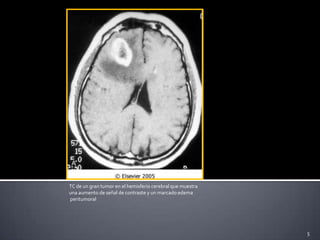

5TC de un gran tumor en el hemisferio cerebral que muestra una aumento de señal de contraste y un marcado edema peritumoral

En estudios radiológicos se puede apreciar un efecto masa así como cambios adyacentes al tumor, por ejemplo edema.En astrocitomas de alto grado se encuentran vasos anormales que presentan extravasaciones y por lo tanto puede visualizarse con medio  de contraste. 7.